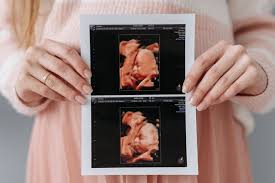

USG 4D: 5 Alasan Kenapa Kamu Harus Mengabadikan Momen Bersama Si Kecil!

usg 4d

Menanti kehadiran buah hati adalah salah satu momen paling membahagiakan dalam hidup. Setiap calon orang tua pasti ingin melihat tumbuh kembang si kecil, bahkan sejak ia masih berada dalam kandungan. Seiring berkembangnya teknologi, keinginan ini bukan lagi sekadar impian. Berkat teknologi pencitraan mutakhir, kini ada USG 4D yang memungkinkan Anda menyaksikan setiap gerak-gerik si kecil … Read more